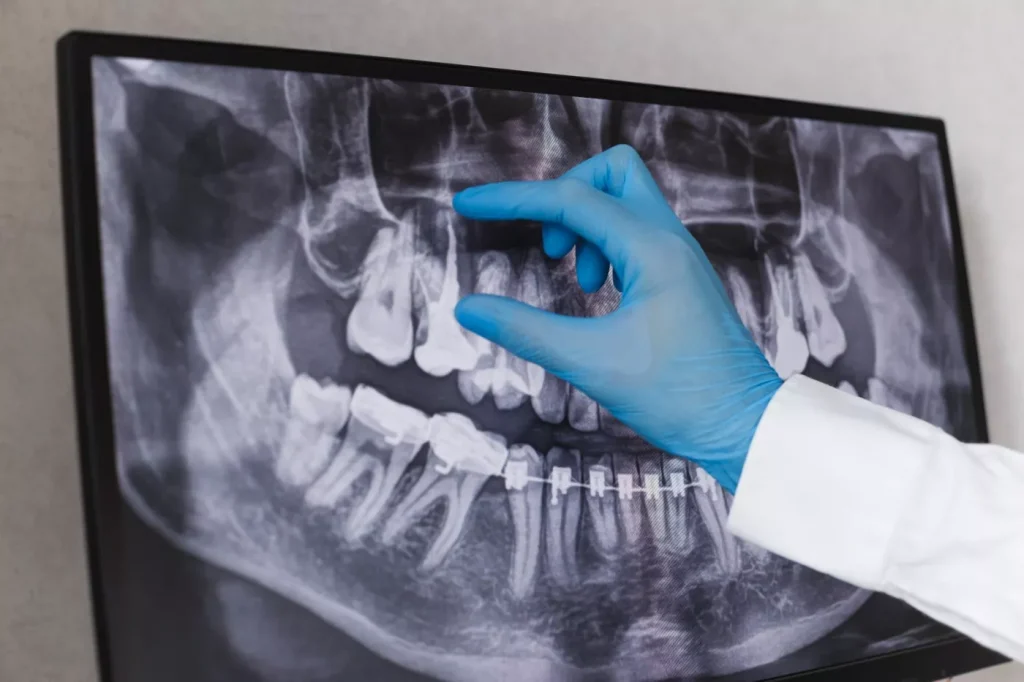

Implantologia orală este specializarea medicinei dentare care beneficiază cel mai mult de avantajele radiologiei dentare.

Efectuarea intervenției de inserare a implantului dentar în mod corect și în condiții de siguranță este esențială pentru succesul integrării implantului în organism și pentru sănătatea orală a pacientului.

În condițiile stomatologiei moderne, precizia acestei intervenții este asigurată de simularea virtuală în prealabil a intervenției, cu ajutorul softurilor specializate, în cadrul imaginilor obținute prin intermediul tomografiei CBCT.

Este importantă evitarea structurilor vitale, precum sinusurile, de aceea, pentru precizie maximă, se stabilește digital traseul exact de inserare a implantului și se printează cu tehnologie 3D, un ghid chirurgical. Acesta arată ca o gutieră, personalizată pe structurile dentare ale pacientului, perforat exact în locul ideal de inserare a implantului, ghidând și direcția de inserare.